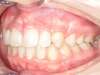

Cas N°6 : Description

Correction majeure des deux arcades dentaires liée à une mandibule rétrusive

Avant

Après